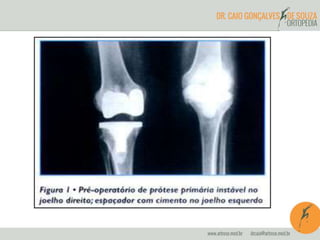

ARTROPLASTIA TOTAL

INDICAÇÕES

• OSTEOARTROSE

AVANÇADA

• DOR

• ACIMA DE 70 ANOS

• COM OU SEM

DEFORMIDADE

CONTRA-INDICAÇÔES

• INSUFICIÊNCIA

QUADRÍCEPS

• INFECÇÃO ATIVA

• ARTRODESE BOA

POSIÇÃO

• OBESIDADE